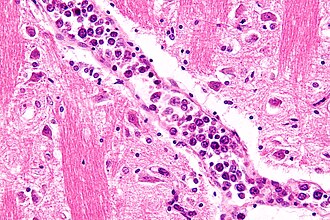

Intravascular lymphoma. H&E stain. | |

| LM | abundant atypical intravascular lymphoid cells (large ~2-3X size of a mature lymphocyte, nucleolus prominent) |

- Abundant atypical intravascular lymphoid cells that are:

- Large (~2-3X size of a mature lymphocyte or RBC).

- Nucleolus prominent.

- It may be hard to find RBCs in the vessels.

- Looks sorta like a DLBCL -- but is intravascular.